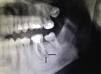

The patient was a 32-year-old man with no past history of interest. He was seen in dermatology outpatients for a tumor in the form of a cutaneous horn sunken into the skin over the left horizontal ramus of the mandible (Fig. 1). Examination revealed no alterations of the oral cavity. The patient stated that the region was tender. He had applied topical treatment with 2% mupirocin ointment without improvement. B mode skin ultrasound (Esaote, Genoa, Italy) using an 18MHz probe revealed a slightly tortuous, relatively well-defined, hypoechoic linear structure that extended to the surface of the cortical bone of the mandible (Fig. 2). Doppler study showed blood vessels in the area around the tract, suggestive of inflammation, and a poorly defined hypoechoic outline in B mode (Fig. 3). With a diagnosis of cutaneous odontogenic sinus, the patient was referred to the maxillofacial surgery department, where the study was completed with orthopantomography. This x-ray study revealed a radiolucent image that surrounded the apex of the posterior root of the left first molar (Fig. 4). Conservative treatment was performed with endodontia and restoration with an amalgam filling, leading to resolution of the cutaneous sinus in 20 days.